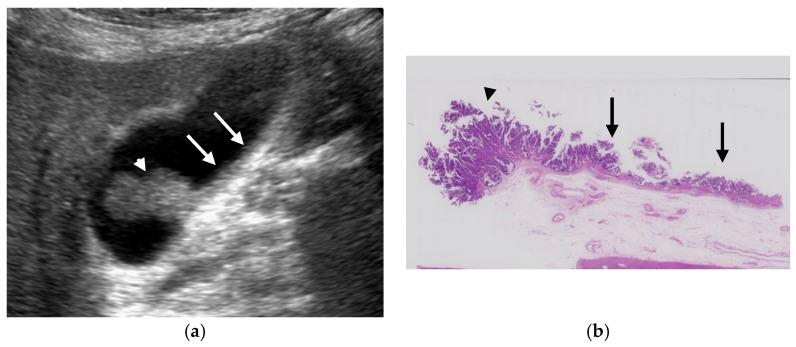

The most important role of ultrasound (US) in the management of gallbladder (GB) lesions is to detect lesions earlier and differentiate them from GB carcinoma (GBC). To avoid overlooking lesions, postural changes and high-frequency transducers with magnified images should be employed. GB lesions are divided into polypoid lesions (GPLs) and wall thickening (GWT). For GPLs, classification into pedunculated and sessile types should be done first. This classification is useful not only for the differential diagnosis but also for the depth diagnosis, as pedunculated carcinomas are confined to the mucosa. Both rapid GB wall blood flow (GWBF) and the irregularity of color signal patterns on Doppler imaging, and heterogeneous enhancement in the venous phase on contrast-enhanced ultrasound (CEUS) suggest GBC. Since GWT occurs in various conditions, subdividing into diffuse and focal forms is important. Unlike diffuse GWT, focal GWT is specific for GB and has a higher incidence of GBC. The discontinuity and irregularity of the innermost hyperechoic layer and irregular or disrupted GB wall layer structure suggest GBC. Rapid GWBF is also useful for the diagnosis of wall-thickened type GBC and pancreaticobiliary maljunction. Detailed B-mode evaluation using high-frequency transducers, combined with Doppler imaging and CEUS, enables a more accurate diagnosis.

超声(US)在胆囊(GB)病变管理中的最重要作用是更早地检测病变并将其与胆囊癌(GBC)区分开来。为避免漏诊病变,应采用体位改变以及具有放大图像的高频探头。GB病变分为息肉样病变(GPLs)和胆囊壁增厚(GWT)。对于GPLs,应首先分为有蒂型和无蒂型。这种分类不仅有助于鉴别诊断,也有助于深度诊断,因为有蒂癌局限于黏膜层。胆囊壁血流(GWBF)快速、多普勒成像时彩色信号模式不规则以及对比增强超声(CEUS)静脉期不均匀强化均提示GBC。由于GWT可在多种情况下出现,将其细分为弥漫性和局灶性形式很重要。与弥漫性GWT不同,局灶性GWT是GB特有的,且GBC发生率更高。最内层高回声层的连续性中断和不规则以及GB壁层结构不规则或破坏提示GBC。快速GWBF对壁增厚型GBC和胰胆管汇合异常的诊断也有帮助。使用高频探头进行详细的B超评估,结合多普勒成像和CEUS,可实现更准确的诊断。